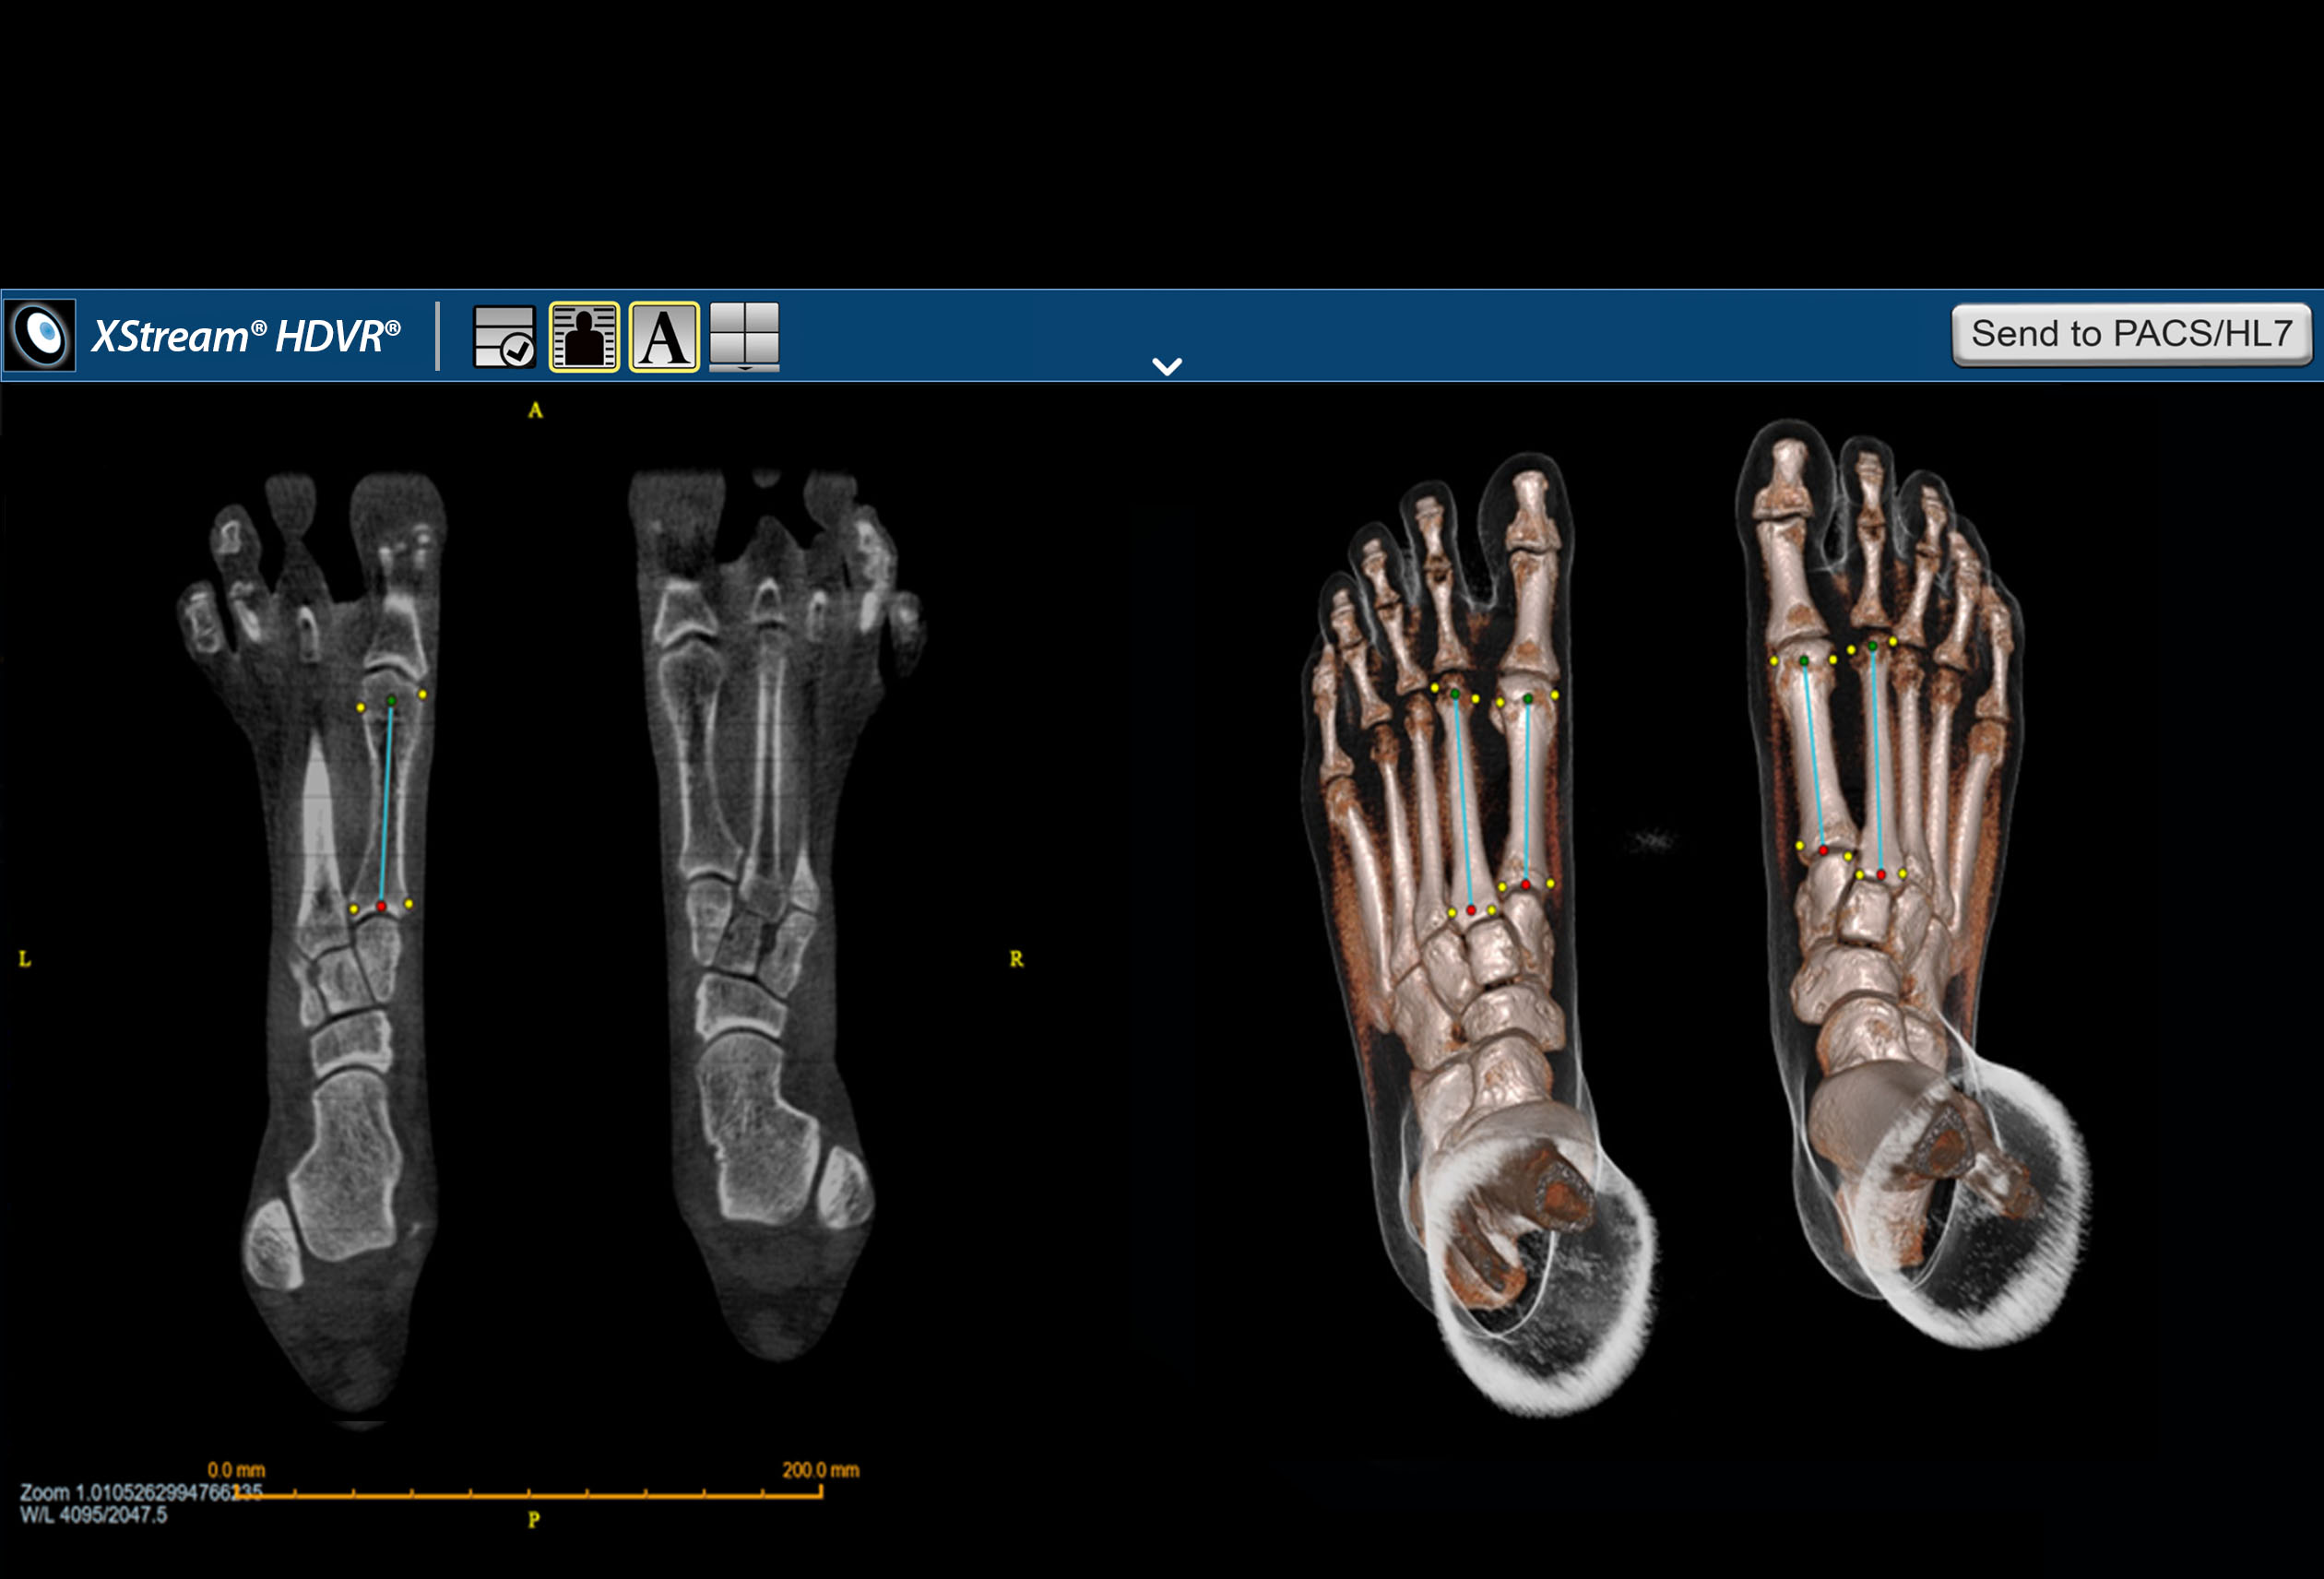

F.A.S.T. Ortho Workflow

F.A.S.T. Ortho Workflow